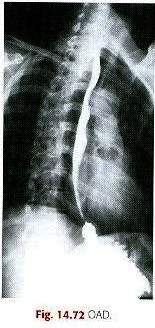

OAD (35° a 40°)

Estruturas Mostradas:

O esôfago deve ser visível entre a coluna vertebral e

o coração. (A posição OAD fornece

maior visibilidade anatômica entre as

vértebras e o coração que a posição

OAE.)

Posição:

A adequada rotação do corpo projeta o esôfago entre a coluna

vertebral e o coração. Se o esôfago

está situado sobre a coluna vertebral,

maior rotação é necessária. O

esôfago é inteiramente preenchido por contraste.